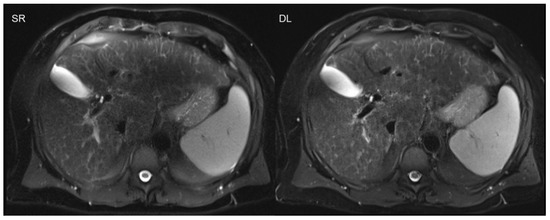

- Almansour, H.; Gassenmaier, S.; Nickel, D.; Kannengiesser, S.; Afat, S.; Weiss, J.; Hoffmann, R.; Othman, A.E. Deep Learning-Based Superresolution Re-construction for Upper Abdominal Magnetic Resonance Imaging: An Analysis of Image Quality, Diagnostic Confidence, and Lesion Conspicuity. Investig. Radiol. 2021, 56, 509–516. [Google Scholar] [CrossRef] [PubMed]

- Gassenmaier, S.; Afat, S.; Nickel, D.; Kannengiesser, S.; Herrmann, J.; Hoffmann, R.; Othman, A.E. Application of a Novel Iterative Denoising and Image Enhancement Technique in T1-Weighted Precontrast and Postcontrast Gradient Echo Imaging of the Abdomen: Improvement of Image Quality and Diagnostic Confidence. Investig. Radiol. 2021, 56, 328–334. [Google Scholar] [CrossRef] [PubMed]

- Gassenmaier, S.; Herrmann, J.; Nickel, D.; Kannengiesser, S.; Afat, S.; Seith, F.; Hoffmann, R.; Othman, A.E. Image Quality Improvement of Dynamic Contrast-Enhanced Gradient Echo Magnetic Resonance Imaging by Iterative Denoising and Edge Enhancement. Investig. Radiol. 2021, 56, 465–470. [Google Scholar] [CrossRef]

- Afat, S.; Wessling, D.; Afat, C.; Nickel, D.; Arberet, S.; Herrmann, J.; Othman, A.E.; Gassenmaier, S. Analysis of a Deep Learning-Based Superresolution Algorithm Tailored to Partial Fourier Gradient Echo Sequences of the Abdomen at 1.5 T: Reduction of Breath-Hold Time and Improvement of Image Quality. Investig. Radiol. 2021. [Google Scholar] [CrossRef] [PubMed]